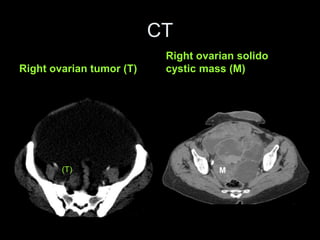

Pseudomyxoma peritonei (PMP) is a rare condition characterized by gelatinous ascites resulting from the rupture of appendiceal mucinous tumors, leading to significant abdominal complications. The incidence is approximately 2 cases per million per year, with a predominance in females, and diagnosis often relies on imaging techniques like ultrasound and CT scans. Effective treatment involves cytoreductive surgery combined with hyperthermic intraperitoneal chemotherapy (HIPEC) to manage disease progression and improve outcomes.